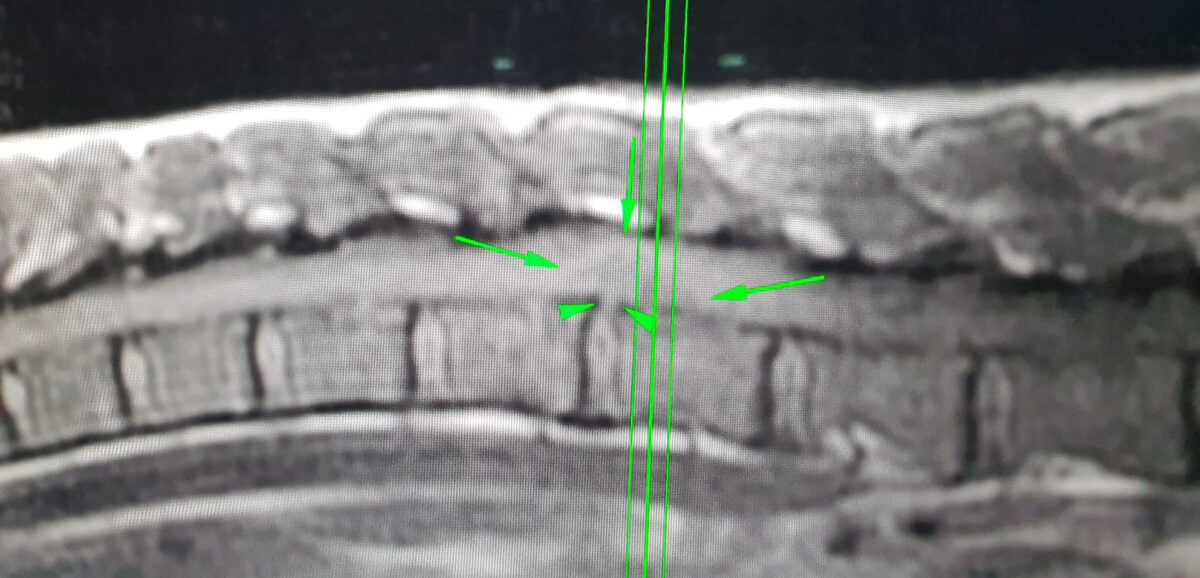

hernia capitan

De hernia bij Capitán, een beknelde zenuw tussen de T14-L1 wervels.

Er was dringend onderzoek nodig, dus we brachten Capitán naar het Anicura Valencia Sur Dierenziekenhuis. Hier werd een MRI-scan werd uitgevoerd om uit te zoeken wat er aan de hand was. Uit de scan bleek dat Capitan een hernia had tussen de T14-L1 wervels, met ernstige druk op het ruggenmerg. Dit zorgde ervoor dat hij pijn had en zijn onderlichaam niet kon bewegen.